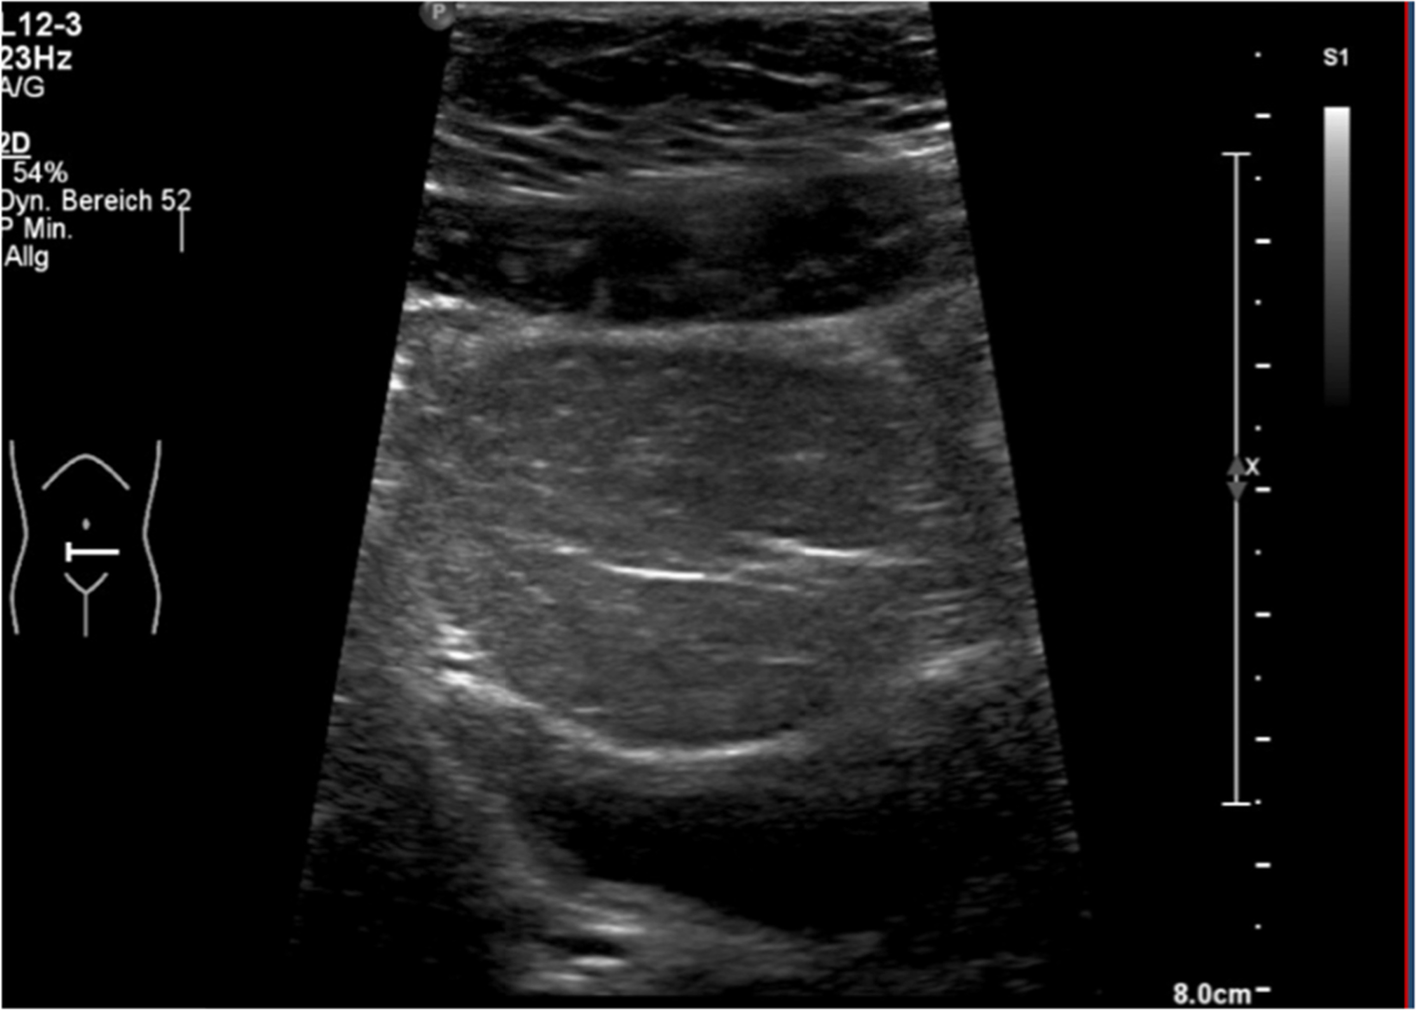

The lifetime risk to develop endometrial carcinoma in women is reported to be 19–28% [19, 25] compared with the general population with 2.1% with a mean age of 69 years [31]. Except for one 16-year-old girl with granulosa cell tumor, gonadal tumors were not described in PHTS [3]. Testicular lipomatosis is described in adult males with PTEN gene mutation. We recommend testicular ultrasound at the beginning of puberty around the age of 10 years. The cumulative lifetime risk (age 70 years) for renal cancer is elevated and appraised to be around 15% (CI = 6%, 32%) [25]. As the youngest patient with a PHTS associated renal cell carcinoma was diagnosed at the age of 11 years [3], we recommend abdominal ultrasound once every year, starting with diagnosis, even though most cases of renal tumors were reported in adult subjects.

Lipomatosis

A lipoma may develop a remarkable size and may therefore have space compromising effects, depending on their localization (Fig. 4). Size and growth might be monitored by ultrasound or MRI scan. As long as there are no space-compromising effects or cosmetic impairments, lipomas do not need an intervention.

Fig. 4

Intraabdominal lipoma compromising urinary bladder in a 10-year-old girl